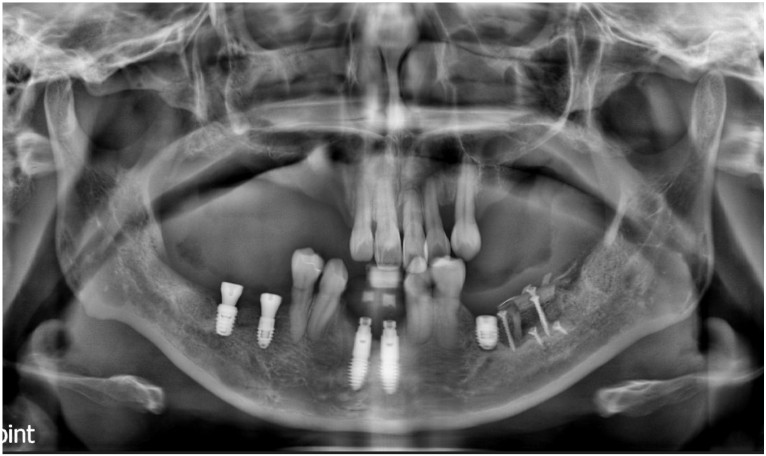

먼저 구강 내를

확인해 보았더니

다수 치아의 상실로 인해

치아의 배열이 흐트러져 있고,

잔존 치아들도

동요도가 심한 상태였는데요.

정밀한 검사를 위해

파노라마 사진을

촬영해 보았더니

만성 치주염으로 인해

다수 치아 상실과

심각한 골소실이 보였으며

이로 인해 양측 어금니 부위의

교합 및 수직 고경이 소실된 상태였습니다.